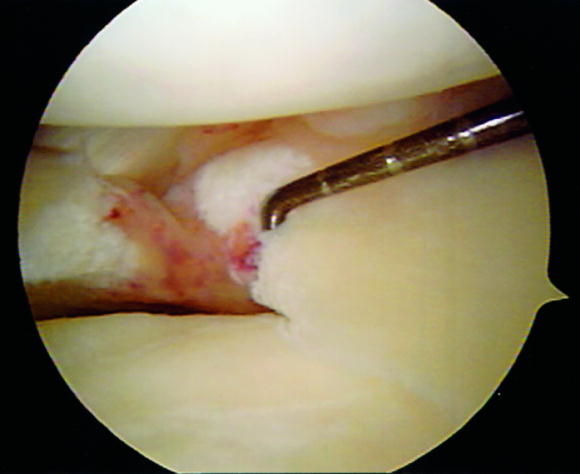

Η θεραπεία της ρήξης των μηνίσκων είναι συνήθως χειρουργική με αρθροσκόπηση. Κατά την διάρκεια του χειρουργείου ο χειρουργός αφαιρεί το σπασμένο (ρηχθέν) τμήμα του μηνίσκου (αυτή είναι η συνηθέστερη πρακτική) ή όταν οι συνθήκες το επιτρέπουν προχωρά σε συρραφή του μηνίσκου.

- Arthroscopic meniscal repair.